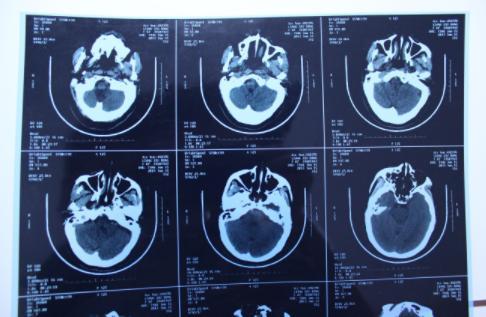

經(jīng)過了疫情的一波沖擊,大部分人都經(jīng)歷了一次新冠病毒的感染,陽康之后很多人都選擇拍胸部CT查看自己的身體情況,當(dāng)人們在看到自己的檢查單上寫著”肺部纖維灶“后嚇了一跳,大部分人詢問的問題都是”自己的肺部是不是纖維化了“、“肺部有玻璃陰影要緊嗎”?

對于人們最關(guān)注的這些問題,上海市胸科醫(yī)院呼吸與重癥醫(yī)學(xué)科副主任李峰表示,不必過度緊張,大部分人都只是出現(xiàn)了感染后的肺間質(zhì)異常,本身是沒有特別的其他癥狀,就像是一個傷痕,之后會慢慢恢復(fù)的,無需過多擔(dān)心,李峰表示,當(dāng)人在眼眶后檢查胸部CT,的確會發(fā)現(xiàn)肺部會有一些磨玻璃影,磨玻璃小結(jié)節(jié)等情況,這都是由于感染病毒之后才出現(xiàn)的,一般情況下不會再擴大,而且過一段時間就會慢慢康復(fù)。